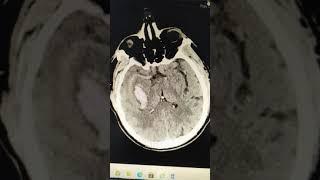

Hemorrhagic Stroke during hypertensive crisis 60yo M

Hemorrhagic Stroke during hypertensive crisis 60yo M